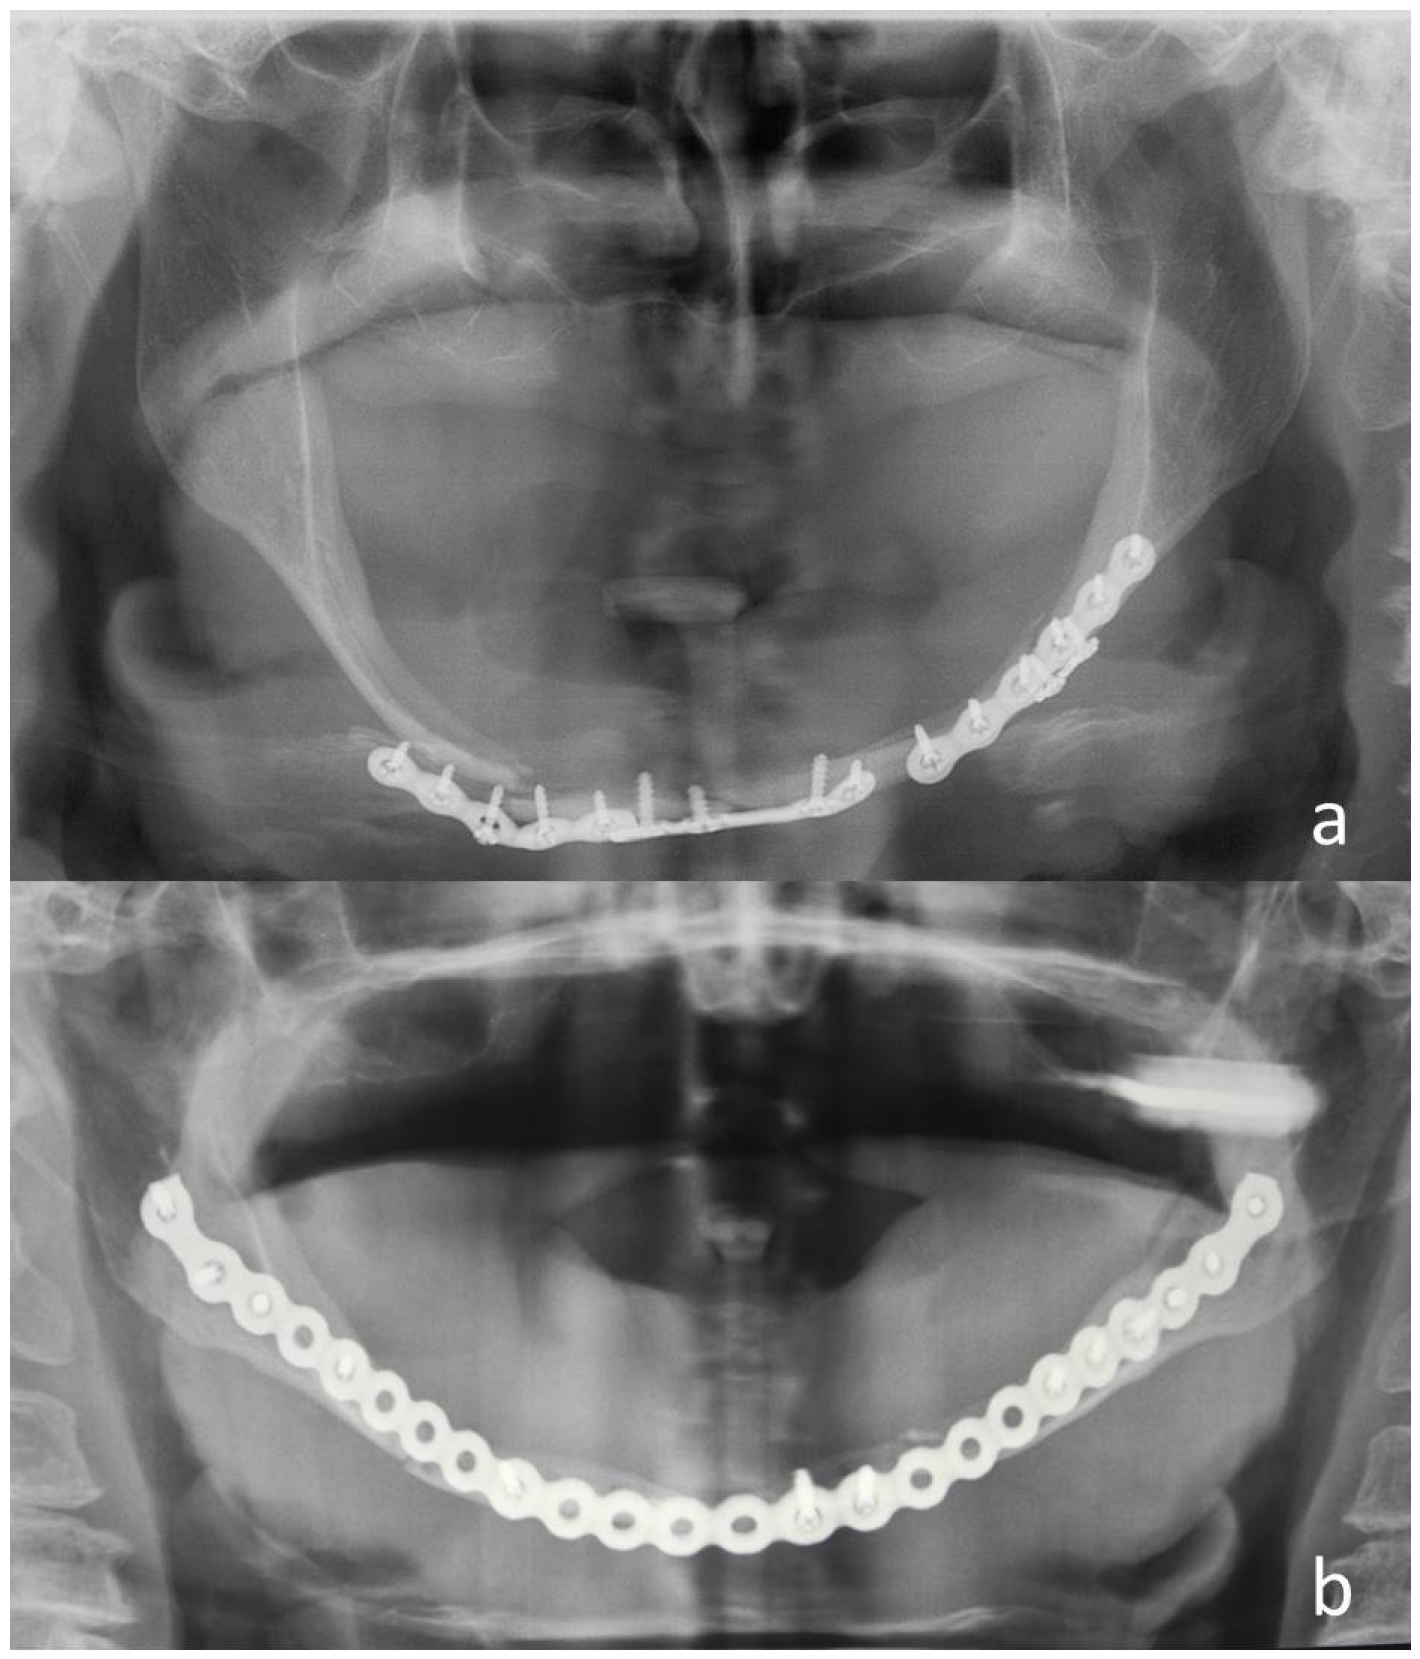

| N | Sex | Age | Etiology | Mandibular Fracture Sites Associated | Approach | Treatment | Hospitalization (Days) |

|---|---|---|---|---|---|---|---|

| 1 | M | 18 | Sport | None | Intraoral | 2 plates 1.0 mm bilateral | 4 |

| 2 | F | 19 | RTA | None | Intraoral | 1 plate 1.0 mm right 2 plates 1.0 mm left | 5 |

| 3 | M | 19 | RTA | None | Intraoral | 2 plates 1.0 mm bilateral | 5 |

| 4 | M | 33 | RTA | None | Intraoral | 1 plate 1.5 mm left 2 plates 1.0 mm right | 9 |

| 5 | M | 56 | Work | None | Intraoral | 2 plates 1.0 mm bilateral | 21 |

| N | Sex | Age | Etiology | Mandibular Fracture Sites Associated | Atrophy Degree * | Approach | Treatment | Hospitalization (Days) |

|---|---|---|---|---|---|---|---|---|

| 6 | M | 37 | RTA | None | I | Extraoral | 1 plate 1.5 mm right 1 plate 1.0 mm left | 5 |

| 7 | F | 49 | Fall | None | I | Extraoral | Plate 2.0 mm | 9 |

| 8 | M | 55 | Assault | Symphysis | I | Intraoral | 2 plates 1.0 mm left 1 plate 1.0 mm right | 3 |

| 9 | M | 55 | Work | None | I | Intraoral | 1 plate 1.5 mm bilateral | 6 |

| 10 | M | 60 | Work | None | I | Intraoral | 1 plate 1.5 mm bilateral | 3 |

| 11 | M | 56 | Fall | None | II | Extraoral | 2 plates 1.0 mm bilateral | 4 |

| 12 | F | 76 | Fall | None | II | Extraoral | Plate 2.0 mm | 7 |

| 13 | M | 77 | Fall | None | II | Extraoral | 2 plates 1.0 mm bilateral | 6 |

| 14 | F | 81 | RTA | None | II | Exraoral | Plate 2.0 mm | 8 |

| 15 | F | 76 | Fall | None | III | Extraoral | 2 plates 1.0 mm bilateral | 3 |

| 16 | F | 80 | Fall | None | III | Extraoral | Plate 2.0 mm | 5 |

| 17 | F | 80 | Fall | None | III | Extraoral | 1 plate 1.5 mm right 1 plate 1.0 mm left | 5 |

| 18 | F | 81 | Fall | Symphysis | III | Extraoral | 1 plate 1.5 mm bilateral | 6 |

| 19 | F | 81 | Fall | None | III | Extraoral | Plate 2.0 mm | 11 |

| 20 | F | 82 | Fall | Symphysis | III | Extraoral | Plate 2.0 mm | 4 |

| 21 | F | 84 | Fall | None | III | Extraoral | Plate 2.0 mm | 6 |

| 22 | F | 84 | Fall | None | III | Extraoral | Plate 2.0 mm | 8 |

| 23 | F | 85 | Fall | None | III | Extraoral | Plate 2.0 mm | 7 |

| 24 | F | 87 | Fall | None | III | Extraoral | Plate 2.0 mm | 7 |

| 25 | M | 90 | RTA | None | III | Extraoral | Plate 2.0 mm | 4 |

| 26 | F | 94 | Fall | None | III | Extraoral | Plate 2.0 mm | 7 |